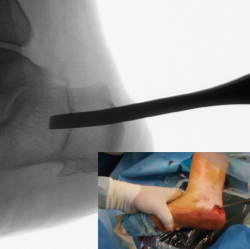

Corrección

Una vez completada, se desplaza la tuberosidad del calcáneo manualmente en la dirección necesaria para la corrección de la deformidad y se introduce un periostotomo a través de la incisión en el escalón que queda tras el desplazamiento para aumentar y mantener dicho desplazamiento. En caso de pie plano valgo, el desplazamiento es medial y se introduce el periostotomo en dirección anterior en la esponjosa del cuerpo del calcáneo para aumentar la traslación (Figuras 7 y 8). En caso de pie cavo varo, el desplazamiento es lateral y se introduce el periostotomo en la esponjosa de la tuberosidad.

Figura 7. Imagen fluoroscópica de la traslación de la tuberosidad con un periostotomo (imagen anteroposterior) y su correspondencia en cirugía.

Se debe mantener la rodilla flexionada para evitar que la tensión del Aquiles nos limite el desplazamiento.

Figura 8. Imagen fluoroscópica de la traslación de la tuberosidad con un periostotomo (imagen axial) y su correspondencia en cirugía.